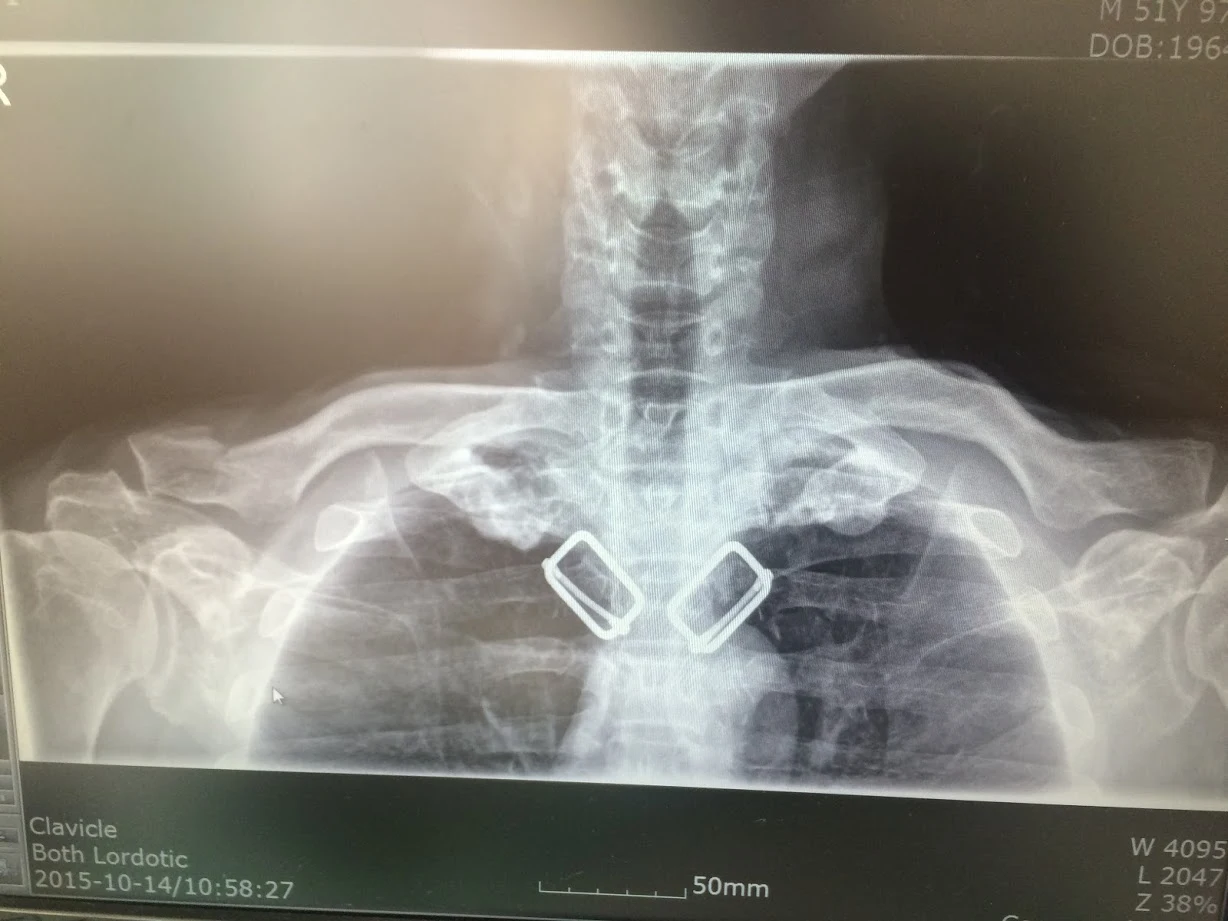

밤새 통증에 시달린 후 24일 낮 삼성창원병원 응급실에 갔다. 엑스레이 검사 결과 쇄골 골절이란다. 8자 밴드(8자 붕대)를 6주간 하고 있어야 한다. 팔꿈치 아래를 움직이는 건 가능하나 어깨를 써서 팔을 올리진 못한다. 당분간 밥도 왼손으로 먹어야 한다. 머리감기도 어렵다.

1.jpg 부러진 내 쇄골 위치와 거의 같다.